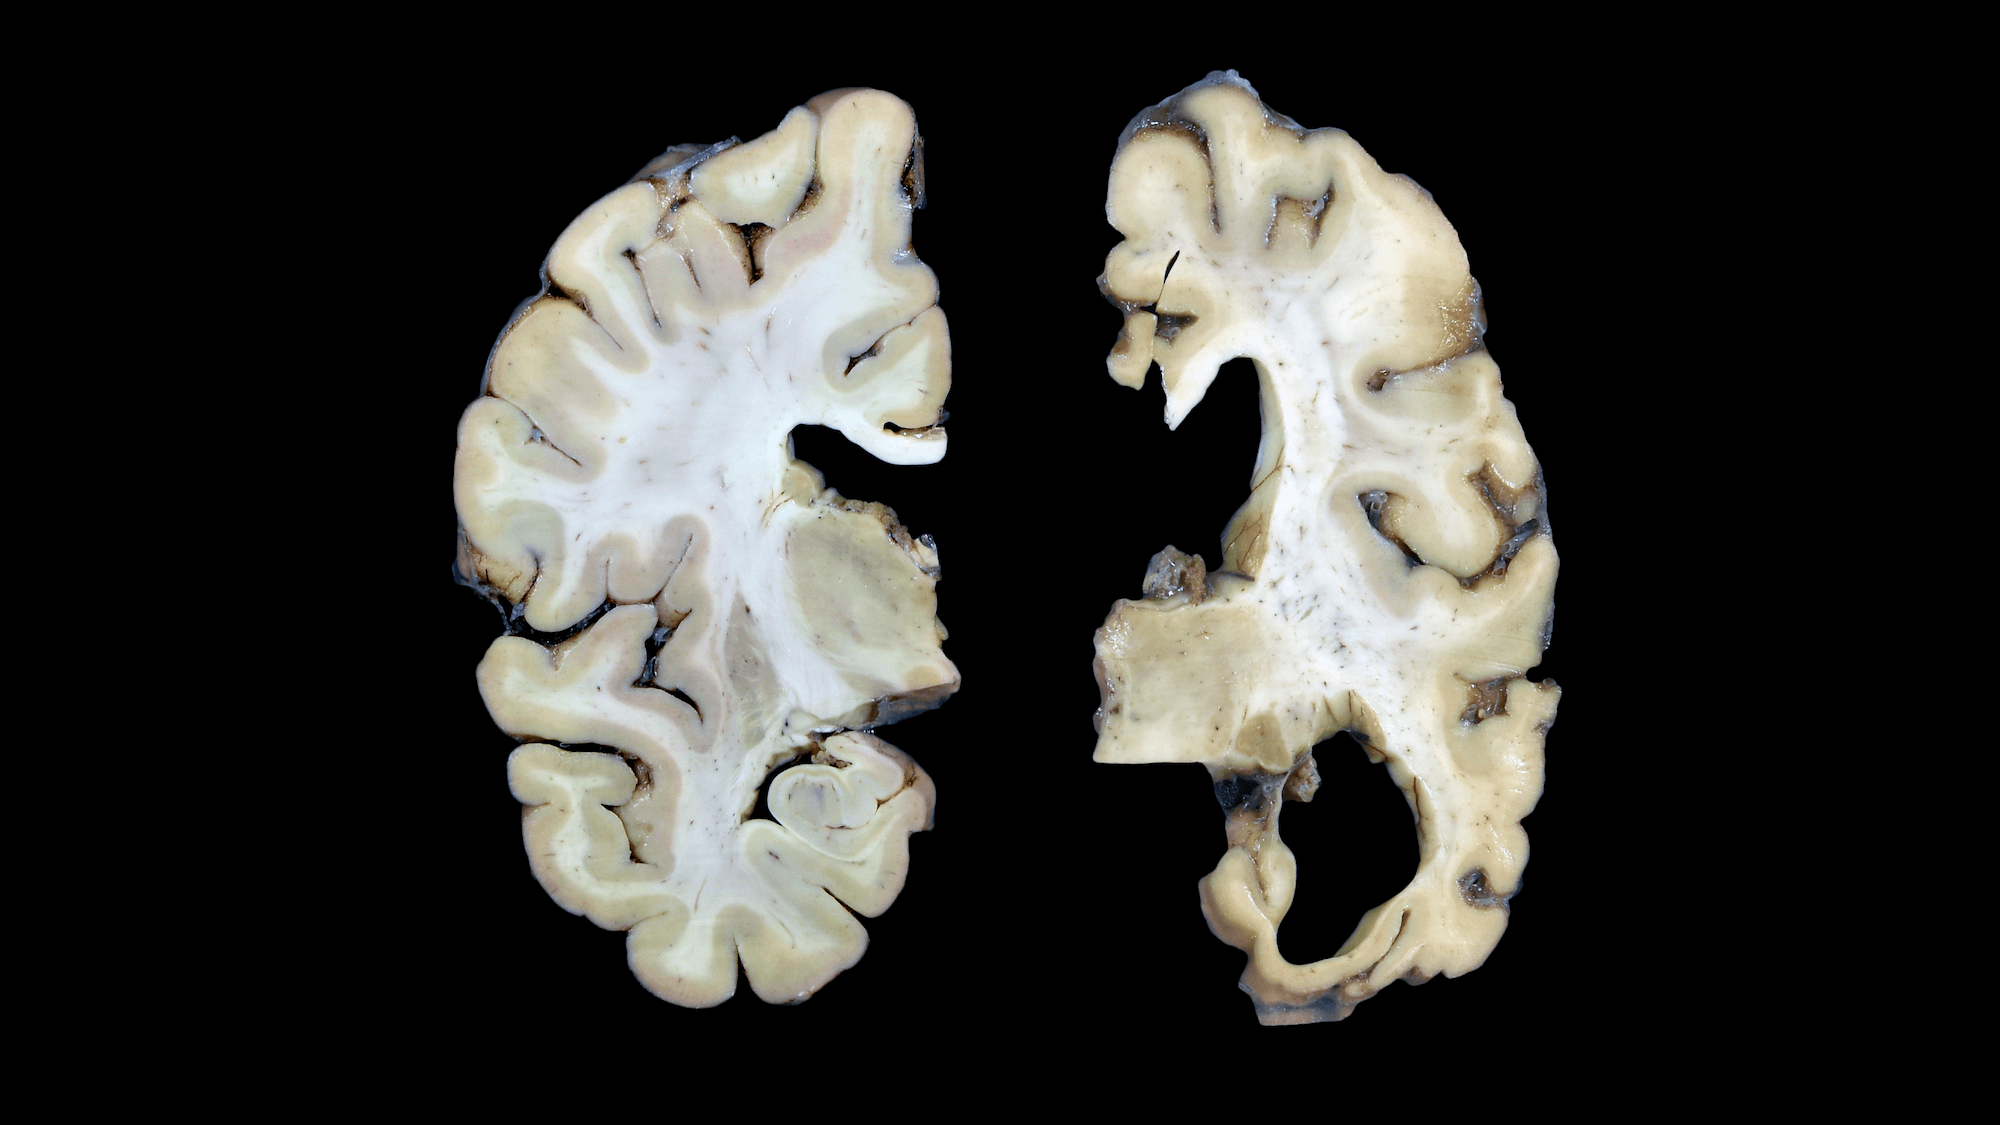

If scientists understood how Alzheimer’s disease starts, they might have a better handle on how to stop it. That’s the premise behind a new $40.5 million collaborative research center in Seattle to build high-resolution maps of Alzheimer’s patients’ brains and identify how their neurons and other brain cells differ from those of healthy people.

By comparing brain cells across patients with different stages of the disease, the researchers will seek to pinpoint how and where the progressive disorder starts — and, ultimately, to find new targets for therapy.

Using these methods to study brains from people across the spectrum of early- to late-stage Alzheimer’s disease should reveal the specific kinds of neurons and other brain cells that are most vulnerable at the beginning of the disease, said Ed Lein, Ph.D., Senior Investigator at the Allen Institute for Brain Science, a division of the Allen Institute, and Lead Investigator of the new center. Such a detailed understanding of Alzheimer’s origins is desperately needed, as many once-promising treatments — primarily aimed at disrupting the disease’s hallmark plaques of beta-amyloid protein in the brain — have failed to benefit patients. Currently, no therapies exist that can halt the progression of Alzheimer’s, which afflicts approximately 5.8 million Americans and, together with other dementias, costs the U.S. an estimated $290 billion every year.

“Alzheimer’s disease is incredibly complicated, in part because different cells and parts of the brain are differentially affected,” said Bradley Hyman, M.D., Ph.D., a professor of neurology and Alzheimer’s researcher at Harvard Medical School and Massachusetts General Hospital who also serves as an advisor to the new research center. “This complexity makes it very difficult to model in experimental systems, and direct examination of the human brain is without a doubt crucial to understanding the disease. The technology developed at the Allen Institute provides a new approach to unravel these mysteries — I can’t wait to see what they discover.”

The experiments will rely on postmortem brain tissue from the University of Washington School of Medicine BioRepository and Integrated Research (BRaIN) laboratory, which supports brain donation from research participants in the Adult Changes in Thought (ACT) study, a long-running study of brain aging led by Kaiser Permanente and UW Medicine, and from UW Medicine’s NIA-funded Alzheimer’s Disease Research Center. The tissue donations will come specifically from participants in these studies who consent to donate their brains to science after they die. The research teams will analyze cells from multiple brain regions from approximately 100 people, ranging from people with normal cognition and little or no sign of Alzheimer’s disease in the brain to those with late stage Alzheimer’s dementia.